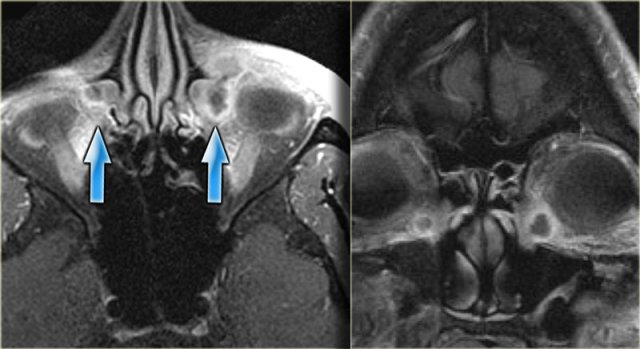

On the left the corresponding MRI.

First study the images, then continue reading.

The findings are:

• Fluid in the right sphenoid sinus (red arrow).

• Hypointense tissue in the left sphenoid sinus (yellow arrows).

• Tracking along the dural margin of the middle cranial fossa (blue arrows).

• Extension into the left zygomatic-masticator space (large yellow arrow).

• Following contrast, there is no solid enhancement of the tissue in the sphenoid space.

Continue with the coronal images.

Lymphoma of sphenoid sinus and skull base Lymphoma of sphenoid sinus and skull base

Coronal images of the same patient: T1 pre-and post-contrast.

Normal aspect of the right Meckel's cave, tissue in the left Meckel's cave extending into the cavernous sinus (blue arrow).

The red arrow points to the dural margin of the cavernous sinus: there is enhancement on both sides of the dura.

The disease wraps around the temporal lobe (green arrow) and extents downward in the foramen ovale (yellow arrow) and into the masticator space.

The asterix indicates normal non-enhancing tissue in the masticator space.

This patient had a lymphoma.

Nine out of ten times an immunocompromised patient will have a fungal infection, in one out of ten it will be a lymphoma.

CT and MR have a complimentary role in this case, but finally a biopsy is called for to differentiate between these two diagnoses, because of different treatment.